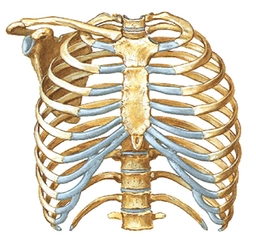

GÖĞÜS GÖREVİ VE ÖZELLİKLERİGöğüs, insan vücudunun önemli bir parçası olup, birçok hayati işlevi yerine getirir. Bu makalede göğsün anatomik yapısı, işlevleri ve sağlık açısından önemi ele alınacaktır. 1. GÖĞÜS ANATOMİSİGöğüs, sternum (göğüs kemiği), kaburgalar ve omurga ile çevrelenmiş bir bölgeyi ifade eder. Bu yapılar, göğüs boşluğunu korur ve iç organların yerleşimini sağlar. Göğüs boşluğunda kalp, akciğerler, büyük damarlar ve diğer hayati organlar bulunur.